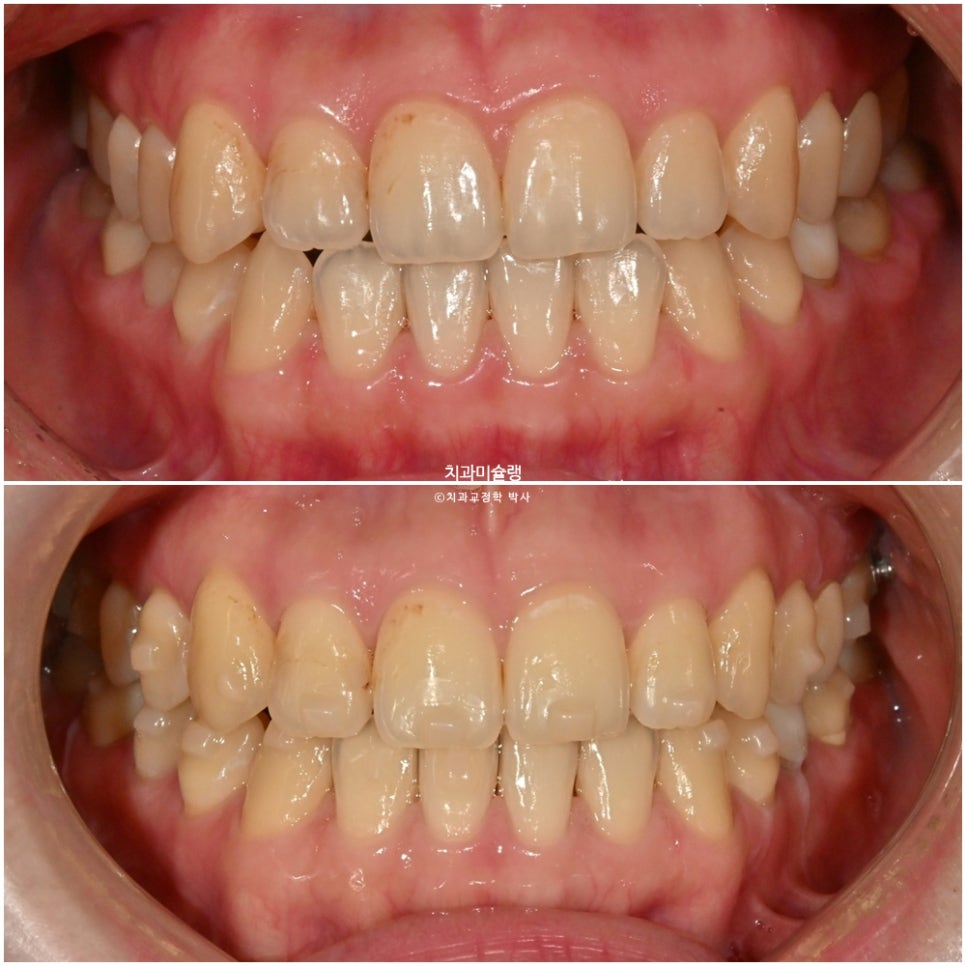

위에서부터 차례대로 교정종료 직후- 피팅 – 무삭제라미네이트 최종 부착 후 모습입니다.

이제 전후 비교 볼게요.

치료 결과

작은어금니에서 작은어금니까지, 앞니 8개에 무삭제라미네이트 젤라미 부착 모습입니다.

잇몸쪽에서 치아 끝단으로 갈수록 음영이 자연스럽게 지는것이 무삭제 라미네이트의 강점 입니다.

두꺼워진 앞니가 측면사진에서 잘 보입니다. 라미네이트 두께가 늘어나도 치아와 잇몸경계는 최대한 얇게 제작해야 잇몸건강에 악영향이 없습니다.

어두워보이던 치아가 환해졌습니다.

스마일라인도 아랫입술과 평행하게 회복되었습니다.

단지 색깔의 변화는 아니고 두께감과 배열 개선의 효과도 큽니다.

치료 도중 입술 필러 치료도 소량 하신것 같네요.